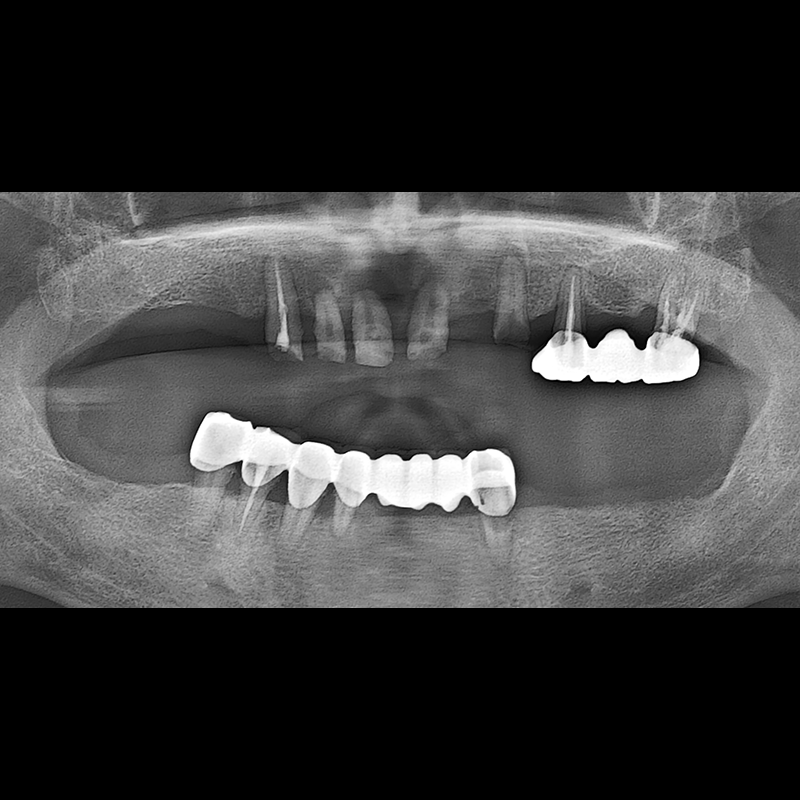

IMPLANT

BEFORE AFTER